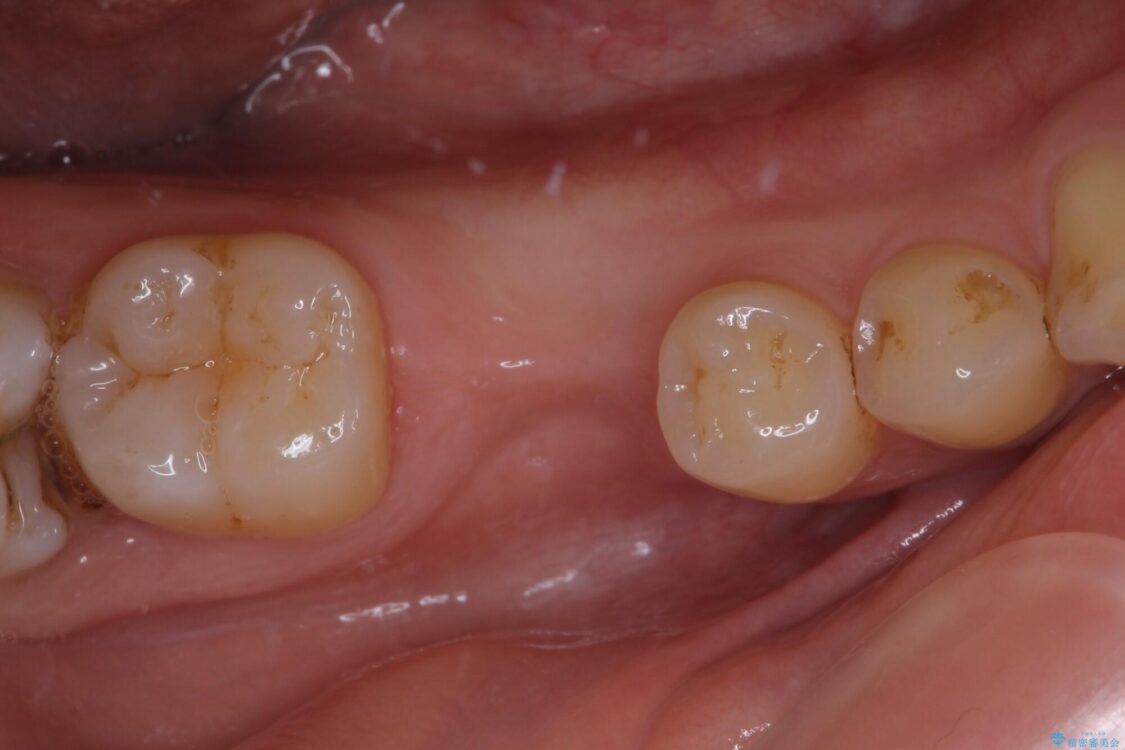

治療途中

• 後戻りでデコボコの前歯 インビザライン矯正治療 治療途中画像